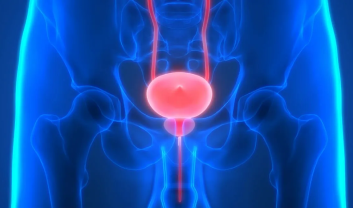

Urinary bladder stones, also known as vesical calculi, are crystallized formations that develop in the bladder....

UTIs manifest with distinctive signs, often causing inconvenience and distress. Recognizing these symptoms is crucial for early intervention...